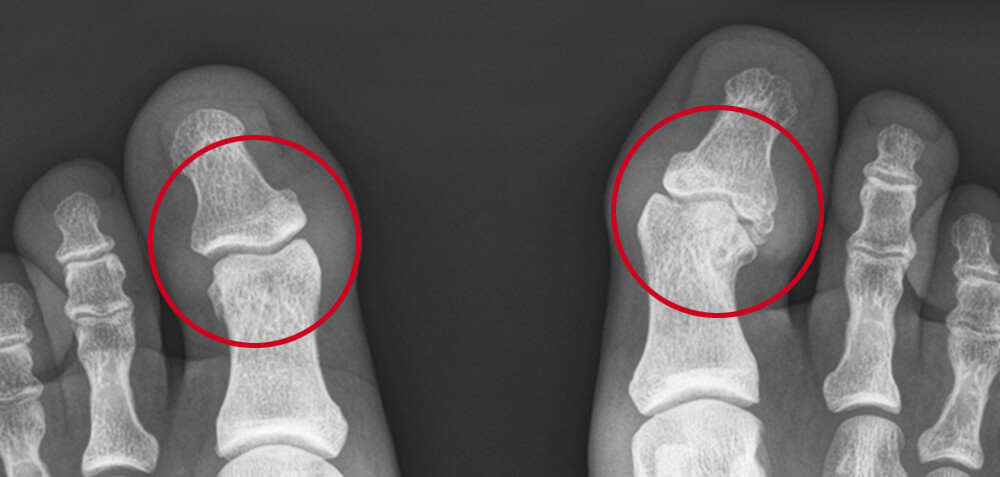

Röntgenfoto van de grote tenen. De grote teen links heeft een normaal IP-gewricht. Rechts ziet u een onregelmatig gewricht.